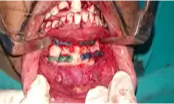

03 April 2023 | Medicover Hospitals | HyderabadA 23yr old male patient brought with history of hit by tractor, With dysmorphic face with active bleeding both nostrils and mouth and the left lower leg. Primary Survey with C spine stabilization: Airway-Not patent, full of bloody secretions, fall back of tongue and fractured symphysis of mandible falls back and cause choking. DifFIcult airway anticipated and intubated with 8.0 size ET tube with in line stabilization of the c-spine and ventilator Support Labored breathing with trachea in midline, dereased chest expansion in right side and decreased air entry.Spo2-80% with 10L o2 100%. with RR-30 breath per minute. Circulation with hemorrhagic control-Heart rate-130 bpm,BP-?,CRT->4sec, 20 ml/kg FLuid resuscitation started and bleeding superficial vessel identiFIed controlled with pressure application and order given to arrange PRBC. Disability-. GCS-E2,V4,M5-11/15, Irritable, Pupils- normal in size reacting to light.Abrasion present in forehead, sutured wound of size 6*3cm in the left anterior part of the neck. X RAY: Chest-Right side Pneumothorax, C spine-Normal, Pelvis-Normal, Left tibia and fibula-Both bone fracture, Left Femur-Displaced lower end. Urinary catheter-Placed, ICD –Placed in Right 5th ics, POP-Applied for both bone leg fracture and femur fracture. Diagnosis Polytrauma with segmental fracture on the mandible, with displaced distal femur fracture, displaced bone fracture on the left leg. Right side pneumothorax.

Treatment: ICD for pneumothorax, ORIF for Mandible, Surgical management for femur Retrograde inter locking nailing.And both bone fracture of leg Inter locking nailing.